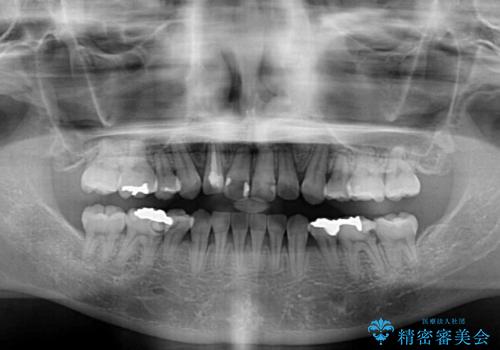

- 前歯のデコボコと上顎の前突感による口の閉じにくさを気にして来院された患者様です。

目立たない装置を希望されたので、上顎が裏側装置のハーフリンガルを選択し、上下左右の小臼歯(計4歯)を抜歯して矯正治療を行うこととしました。

治療期間の目安は3年~3年半でしたが、咬み合わせにより上顎のスペースがなかかな閉じきらず、治療期間が長期化してしまいました。

期間はかかったものの、口元の張り出し感や歯のデコボコが解消され、患者様には大変満足していただけました。